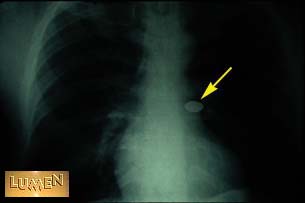

Where is the coin?

Left main bronchus.